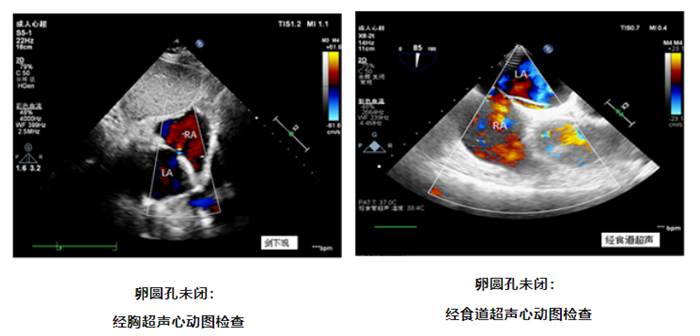

怎样发现卵圆孔未闭

超声心动图是卵圆孔未闭的首选检查,包括经胸超声心动图及经食道超声心动图,都能够评价房间隔解剖结构和分流情况。经胸超声心动图扫查需要透过皮肤、皮下肌肉及脂肪组织对房间隔的分流进行评估,成人受各种因素如肥胖、肺气过多等影响,很难准确诊断及测量 PFO,检查结果可能为假阴性。而经食道超声心动图可清楚观察房间隔解剖结构,是诊断 PFO 的金标准。而超声心动图结合右心声学造影并配合规范的激发试验检查, PFO 的检出率可明显提高。

什么是右心声学造影

右心声学造影,又称为振荡生理盐水增强显影,目前常用振荡的无菌生理盐水或糖盐水配制声学造影剂,由于其产生的微泡较大,不能通过肺循环,只能在右心显影,故称为右心声学造影剂,从而可应用于判断是否存在心内分流和肺内分流。